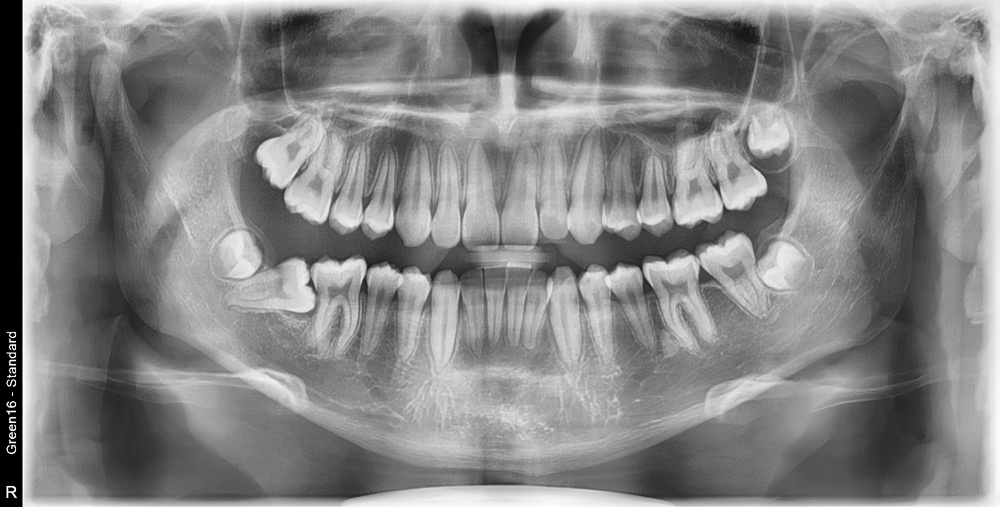

치료 전 사진입니다.